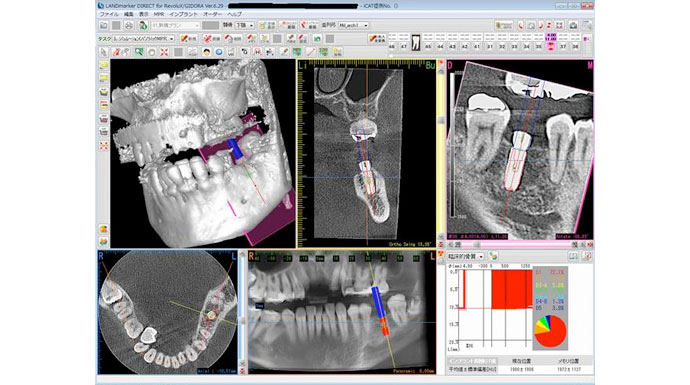

当院では必ずCTレントゲン撮影をし、パソコンでインプラントを行う箇所へのCTシミュレーションを行った後にインプラント治療を進めます。インプラント治療をされる方には全員、CT撮影とCT診断を無料で行っています。

当院はCTを完備しています。こちらはCTシミュレーションソフトの画像です。難しいケースでは術中にもCT撮影を行い、位置や方向を確認しながら施術を進められるので、インプラントを精密に埋め入れることが可能です。安全が最優先なので、これで失敗や事故などを防ぐことができます。

また、シミュレーションを行った方の個人データからインプラントガイドという道具を作った場合は、CT撮影をせずに精密なインプラント治療を行えます(上記のCT画像は、シミュレーションした部位と実際にインプラントを行った後の比較をするためのものです。インプラントの埋め入れ位置や方向、計測したサイズまで精密に行えています)。